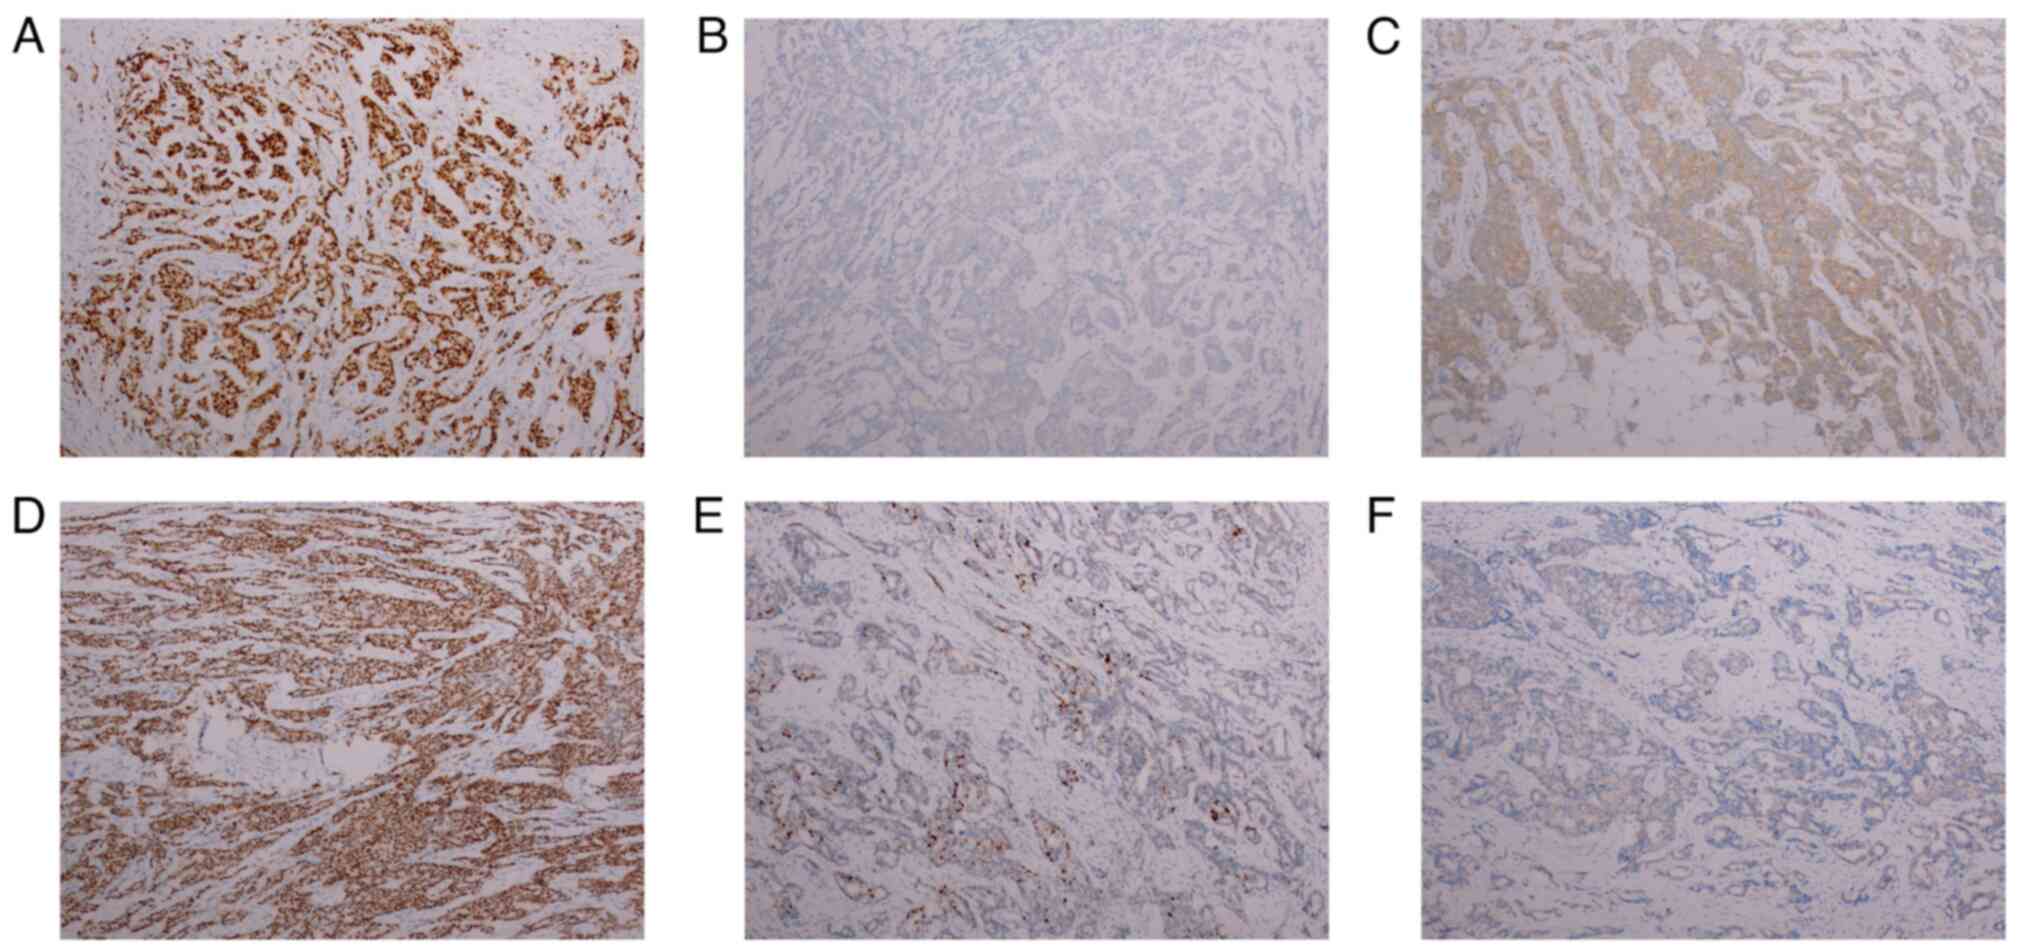

and its location in a non-central area of the breast. Pathology and

immunohistochemistry (IHC) results confirmed a diagnosis of

invasive ductal carcinoma, grade II, with metastases found in 28/35

axillary lymph nodes (Figs. 1B and

C, and 2A-C), 13 days after admission, the

patient was discharged. IHC was performed using paraffin-embedded

tissues; briefly, tissues were removed and immediately immersed in

4% PFA for 6 h for fixation (Room temperature, RT). After

dehydration in a gradient of 70-100% alcohol, it was transparent

using xylene and finally embedded in solid paraffin. Tissue wax

blocks were finally cut into 4 µm thick sections. Tissue processing

and interpretation of results were performed using Roche's

Benchmark GX. EDTAVEGTA pH 8 was selected for antigen repair and

was used for repair using machine parameters (100̊C, 30 min). And

endogenous catalase was closed with 3% hydrogen peroxide for 5 min

(RT). HER2, PR and ER monoclonal antibodies were used to incubate

at 37̊C for 30 min (ready-to-use antibody, Maixin, Fuzhou, China,

HER2: Kit-0043, 0013; ER: Kit-0012), respectively. Secondary

antibodies were incubated with ready-to-use HRP-labeled secondary

antibodies from Roche (Roche, Cat. No 760-500) for 8 min at room

temperature. This was followed by color development using DAB color

solution at room temperature for 8 min (Roche, Cas. No 760-500),

and hematoxylin staining was used for 7 min to show the nuclei

(RT). After gradient dehydration and xylene transparency, the

slices were sealed using neutral resin and observed using an

Olympus ortho-microscope (Light microscope, objective magnification

10X). The patient was admitted to the hospital for chemotherapy

chemotherapy in May. In May 2022, the updated pathology report of

the right breast revealed grade III invasive carcinoma, with

visible vascular embolus and nerve invasion. No cancerous tissues

were found in the nipple or the base margin. Carcinoma metastasis

was identified in all 23 axillary lymph nodes and in all 3 of the

other lymph nodes assessed (Figs.

1E and F, and 2D-F). CT scan showed multiple microscopic